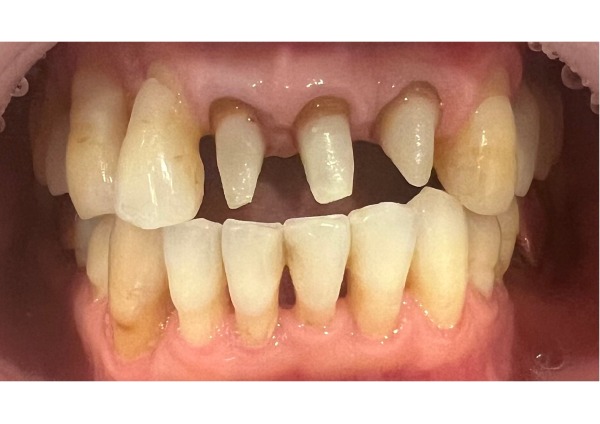

前歯3本は神経がなく、痛みはないものの、歯ぐきが下がったことで茶色く変色した歯根が見えてしまっている状態でした。見た目を気にされていた患者様に治療の選択肢をご提案したところ、「被せ物の色を細かく再現できる」という理由からジルコニアセラミックの被せ物を選択されました。

前歯の被せ物をジルコニアセラミックにしたことで、以前の茶色く変色した歯根の色も気にならず、仕上がりに大変満足されていました。

4日目 前歯3本の被せ物除去し、仮歯を付けました。

5日目 土台を外し、ファイバーコアに変更、型取りを行いました。

6日目 被せ物を仮付けし3ヶ月間経過観察後、本格的に装着しました。